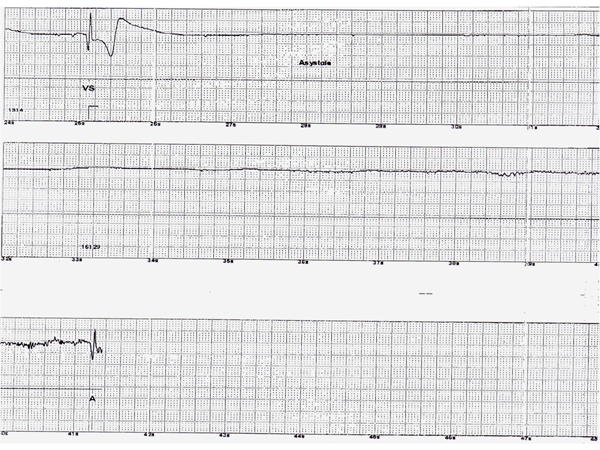

Figure 1

Tracings downloaded from implantable loop recorder shows transition from sinus rhythm to complete heart block and prolonged asystole.

Figure 2

Asystole continues through out the tracing.

A thirty four year old woman was referred to our syncope and autonomic disorder center for evaluation of recurrent unexplained periods of transient loss of consciousness (TLOC) associated with convulsive activity. The episodes would come on suddenly while sitting or standing with little or no prodrome. She would abruptly lose consciousness and fall to the floor. Bystanders reported her to be pale and ashen in color. Witnesses reported that during episodes she would display tonic-colonic like convulsive activity lasting from 1-5 minutes associated with urinary incontinence. The loss of consciousness could last for 30 to 45 minutes. Afterwards the patient was confused and fatigued for the remainder of the day. The patient had undergone multiple evaluations including, 12 lead electrocardiograms, echocardiography, stress testing, tilt table testing and prolonged holter and event monitoring, all of which were unremarkable. Repeated electroencephalograms (including a prolonged inpatient monitoring) were inconclusive and empiric therapy with multiple anti- seizure medications did not alter the frequency or severity of her TLOC. She was labeled as having either refractory epilepsy or conversion disorder. After presentation to our center she underwent placement of an implantable loop recorder (ILR). She later suffered one of her typical TLOC episode associated with witnessed convulsive activity. A download of the device demonstrated that concomitant with the episode of TLOC the ILR had recorded a periods of complete heart block followed by a prolonged periods of asystole, with artifacts consistent with convulsive activity was noted. Prolonged periods of asystole have been reported to result in convulsive activity that may be misdiagnosed as being due to epilepsy (1,2,3). The patient then underwent permanent pacemaker implantation with complete resolution of her TLOC episodes.

This case graphically illustrates the utility of the ILR in establishing the cause of recurrent unexplained TLOC. In addition the tracing demonstrates an interesting sequence of complete heart block followed by prolonged asystole that resulted in TLOC with convulsive activity. Prolonged asystole has been reported to cause abrupt onset, convulsive episodes with prolonged loss of consciousness that at times can be misdiagnosed as epilepsy (1, 2, 3). An ILR can be invaluable in identifying these patients and facilitating prompt therapy (3).